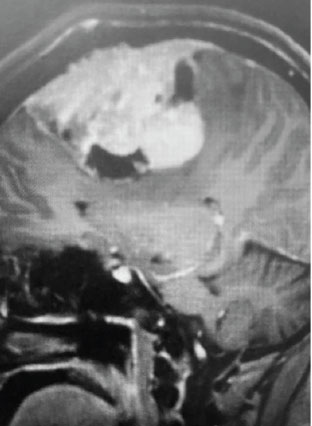

Fig 1. B) Pre-operative, sagittal post-contrast MRI.

This is a 55 year old right-handed woman who was having progressive balance problems. MRI with and without contrast demonstrated a 7 cm partly cystic meningioma involving the left frontal convexity and falx, and encasing the superior sagittal sinus. There was also tumor involvement of part of the convexity skull.

Meningiomas that involve the superior sagittal sinus: Sometimes convexity or falx meningiomas will grow into the superior sagittal sinus. Sometimes the sinus can become completely occluded. Usually this occurs over many years, and as such, the brain has time to develop venous collaterals. So, while in a normal person, sudden occlusion of the superior sagittal sinus could lead to venous infarction or death, the very gradual occlusion that can be seen with meningiomas, does not lead to these problems. Also, if the sinus is filled with tumor and completely occluded, it can usually be safely removed at that segment.